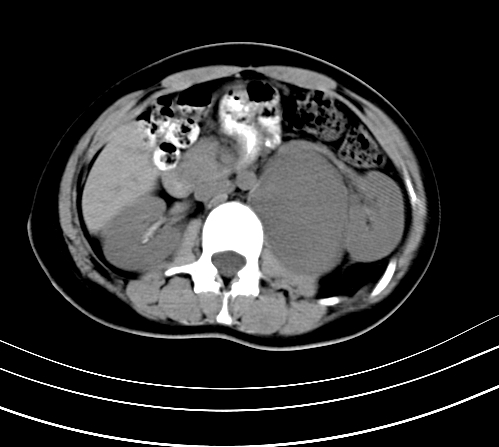

腹部平扫